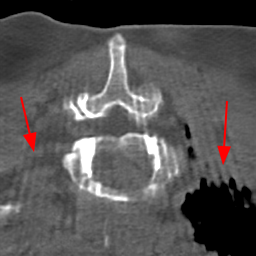

Disentanglement and explicit shape constraints. As shown in Fig. 4, we can see streak metal artifacts nearly everywhere in . M1 can roughly disentangle artifacts and anatomical information but strong vertical artifacts and strange air area appear in (see red arrows of M1 in Fig. 4). For the anatomical structure, M1 learns to segment vertebrae with fully supervised and applied on various CT images, but fails to suppress the false bony structure in and as may misclassify some metal artifacts as bone.

Implicit shape constraints. With , all segmentations are improved with higher Dices and smaller ASDs, see Table 1. As shown in Fig. 4, , and become similar but the high density bone is not correctly segmented in as it maybe treated as metal artifacts. Comparing between M2 and M1, the abnormal air region disappears but metal artifact reduction performance is still not satisfactory.

Anatomy-aware generation. With AADE layer in M3, , and are substantially improved as shown in Table 1. Note, is used as attention map, so we do not expect it to be identical to . In , metal artifacts are further suppressed comparing with M2. Thus, AADE is critical to our anatomy-aware artifact disentanglement framework. With the special structure, can be punished in the image translation and reconstruction processes and the other encoders and generators receive more guidance. However, as shown by blue arrows in Fig. 4, we observe a shadow of vertebra edge of appears in of M3 and the vertebra boundaries get smoothed out in . It may be because sharp edges are encoded as metal artifacts and forced to be added to by artifact consistency loss .

Removal of . To mitigate vertebrae shadows, we remove . The segmentation performance of most images in M4 gets improved because of better synthetic images. Overall, in M4 yields the best segmentation performance for CBCT images with an average Dice of 0.847 and an average ASD of 1.54 mm. For the synthetic images, M4 generates with the best quality and least metal artifacts among all the models. M4 also outputs without vertebra shadows. The results indicate our shape-aware network could preserve anatomical details and transfer the metal artifacts precisely without .